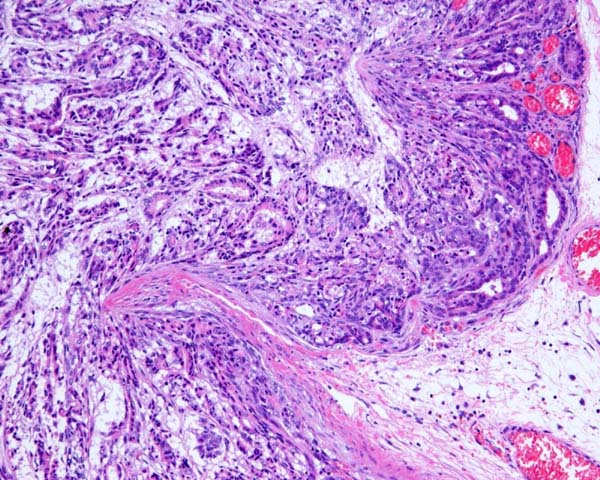

ワンちゃんが乳腺にできた複数のシコリを気にされて来院されました。bilateral mastectomyで対応しました。摘出後の病理組織検査の結果は、「R3-4間腫瘤:乳腺癌(複合型)」でそれ以外は「良性乳腺混合腫瘍」でした。無事元気に退院し、その後再発もなく経過は良好です。よかったね。